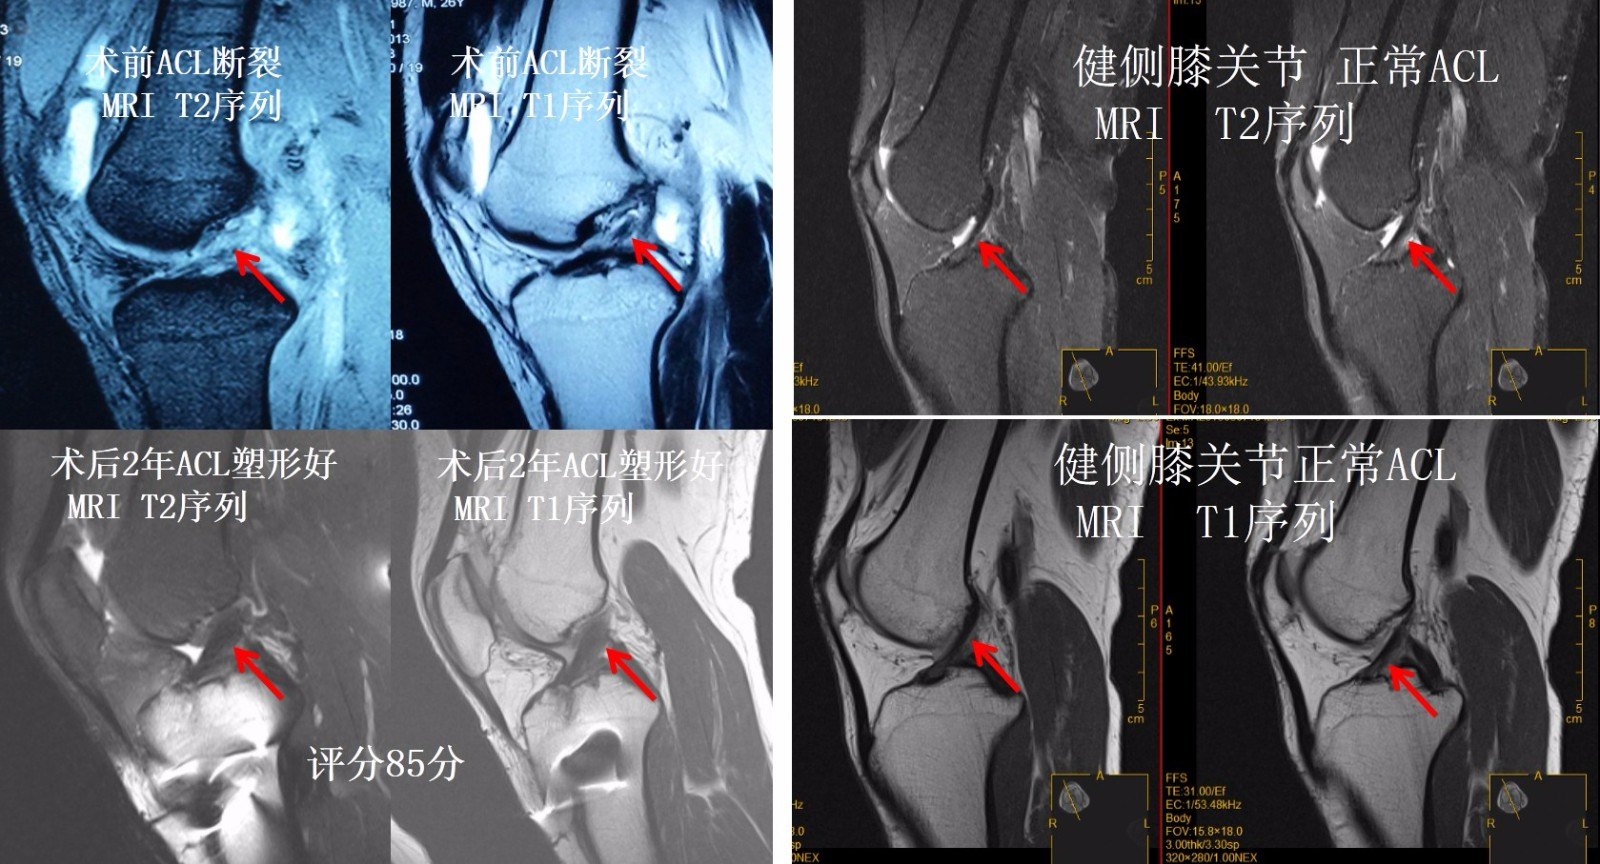

ACL重建后进行MRI评估是评估重建ACL塑形的最直观的非创伤性检查方法。我们的观点认为,如果重建的ACL在MRI上的评分在80分以上(MRI的三个评估指标,总分90分:韧带的容积-30分;韧带的张力-30分;韧带的灰度-30分),术后膝关节功能就恢复好,再次恢复到伤前运动状态的几率就大,重建韧带发生再断裂的风险就低。而且我们在随访过程能根据重建的ACL在MRI上的评分结果调整康复进程,指导患者的运动方法,以利于重建韧带的最终塑形,这个十分重要的。

但是也存在一部分患者在进行前交叉韧带重建后,韧带塑形一直不满意,韧带塑形 变化不明显。术后2年一直韧带塑形变化一直无好转。